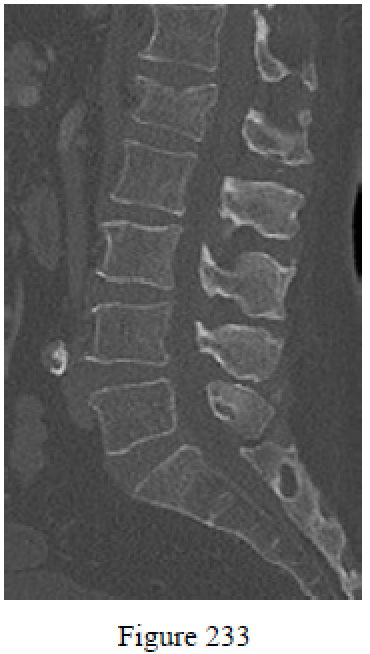

Question 233

Figure 233 is a sagittal CT scan of a 77-year-old woman who has been experiencing back pain for about 1 month. How does an acute fracture appear on an MR image?